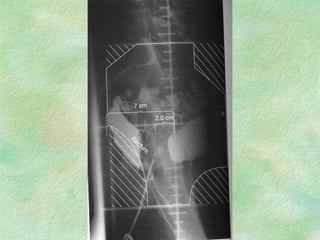

Lateral Field Nodes outlined With solder

Lateral Field Nodesoutlined With solder